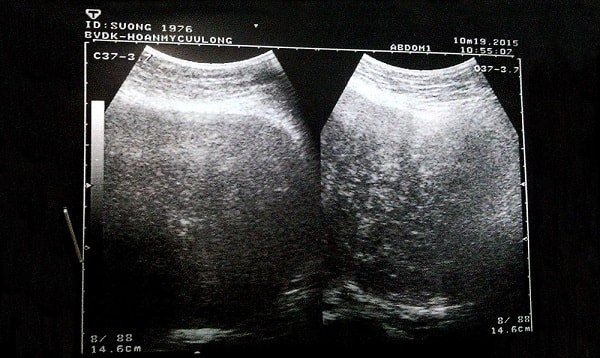

Xét nghiệm hình ảnh học thường được chỉ định để xác định kích cỡ và vị trí của u. Hình ảnh học còn giúp xác định bản chất của u trong bụng. Những phương tiện hình ảnh thường đường dùng là:

- Siêu âm bụng